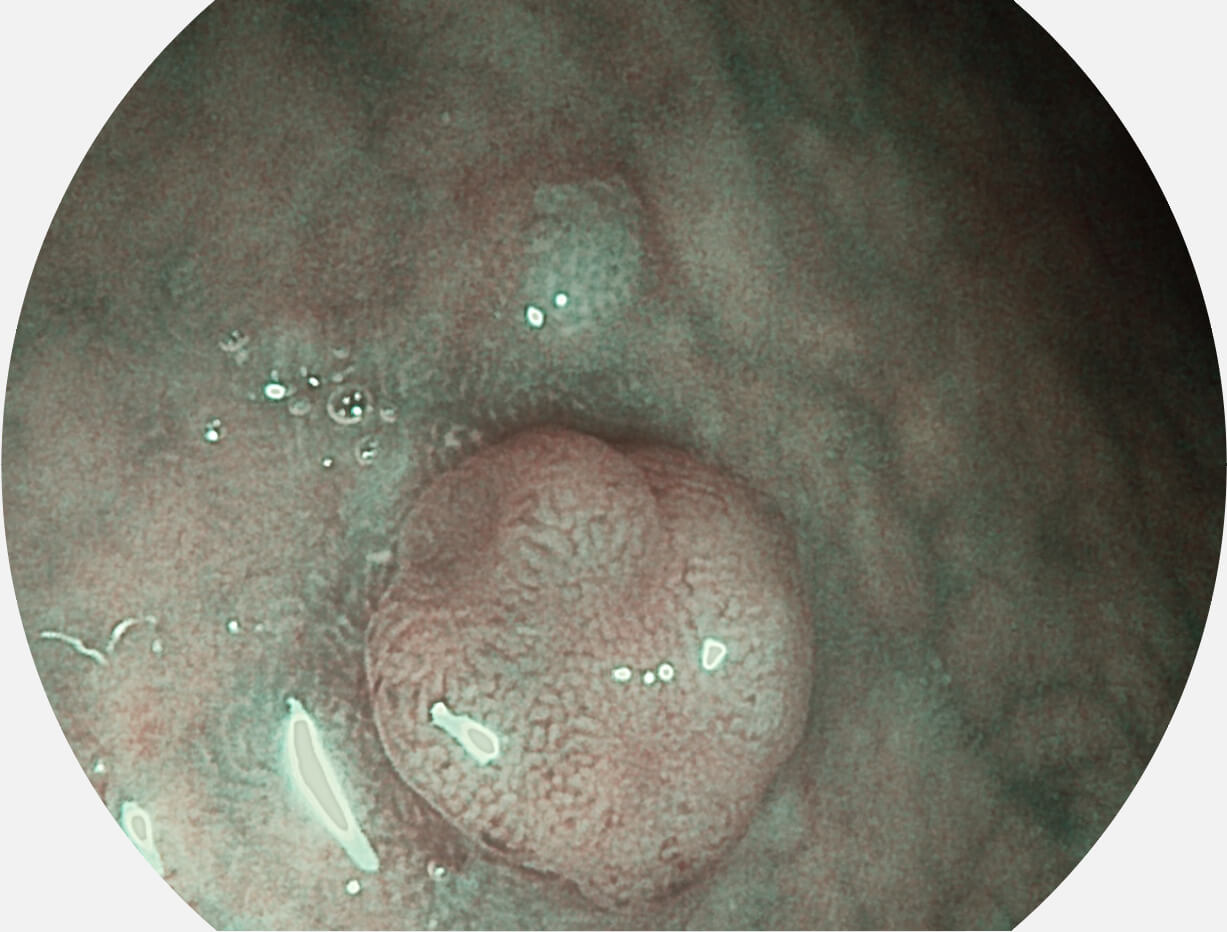

强调浅层黏膜结构的同时,保证照明亮度和提升浅层微血管与中层血管颜色对比度,病变边界更清晰。

VIST图像